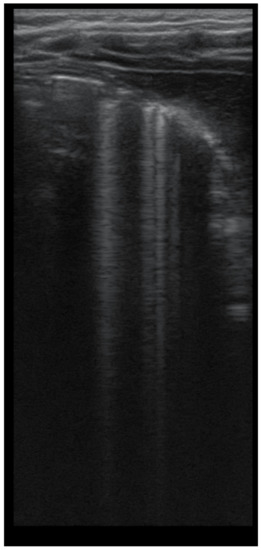

The assessment of LUS sensitivity and specificity in bronchiectasis detection varied with the form of bronchiectasis: for cylindrical bronchiectasis(Figure 8A,B), LUS Se = 77.7%, Sp = 9%, PPV = 80.7%, and NPV = 76.9%, while for saccular bronchiectasis (Figure 7), a moderate Se = 68.4%, with good Sp = 94.9%, PPV = 88.8%, and NPV = 94.7% were found.

Figure 8. (A) CT scan: cylindrical bronchiectasis with mucus plugs (B) LUS: A lines, normal LUS aspect, score = 0.